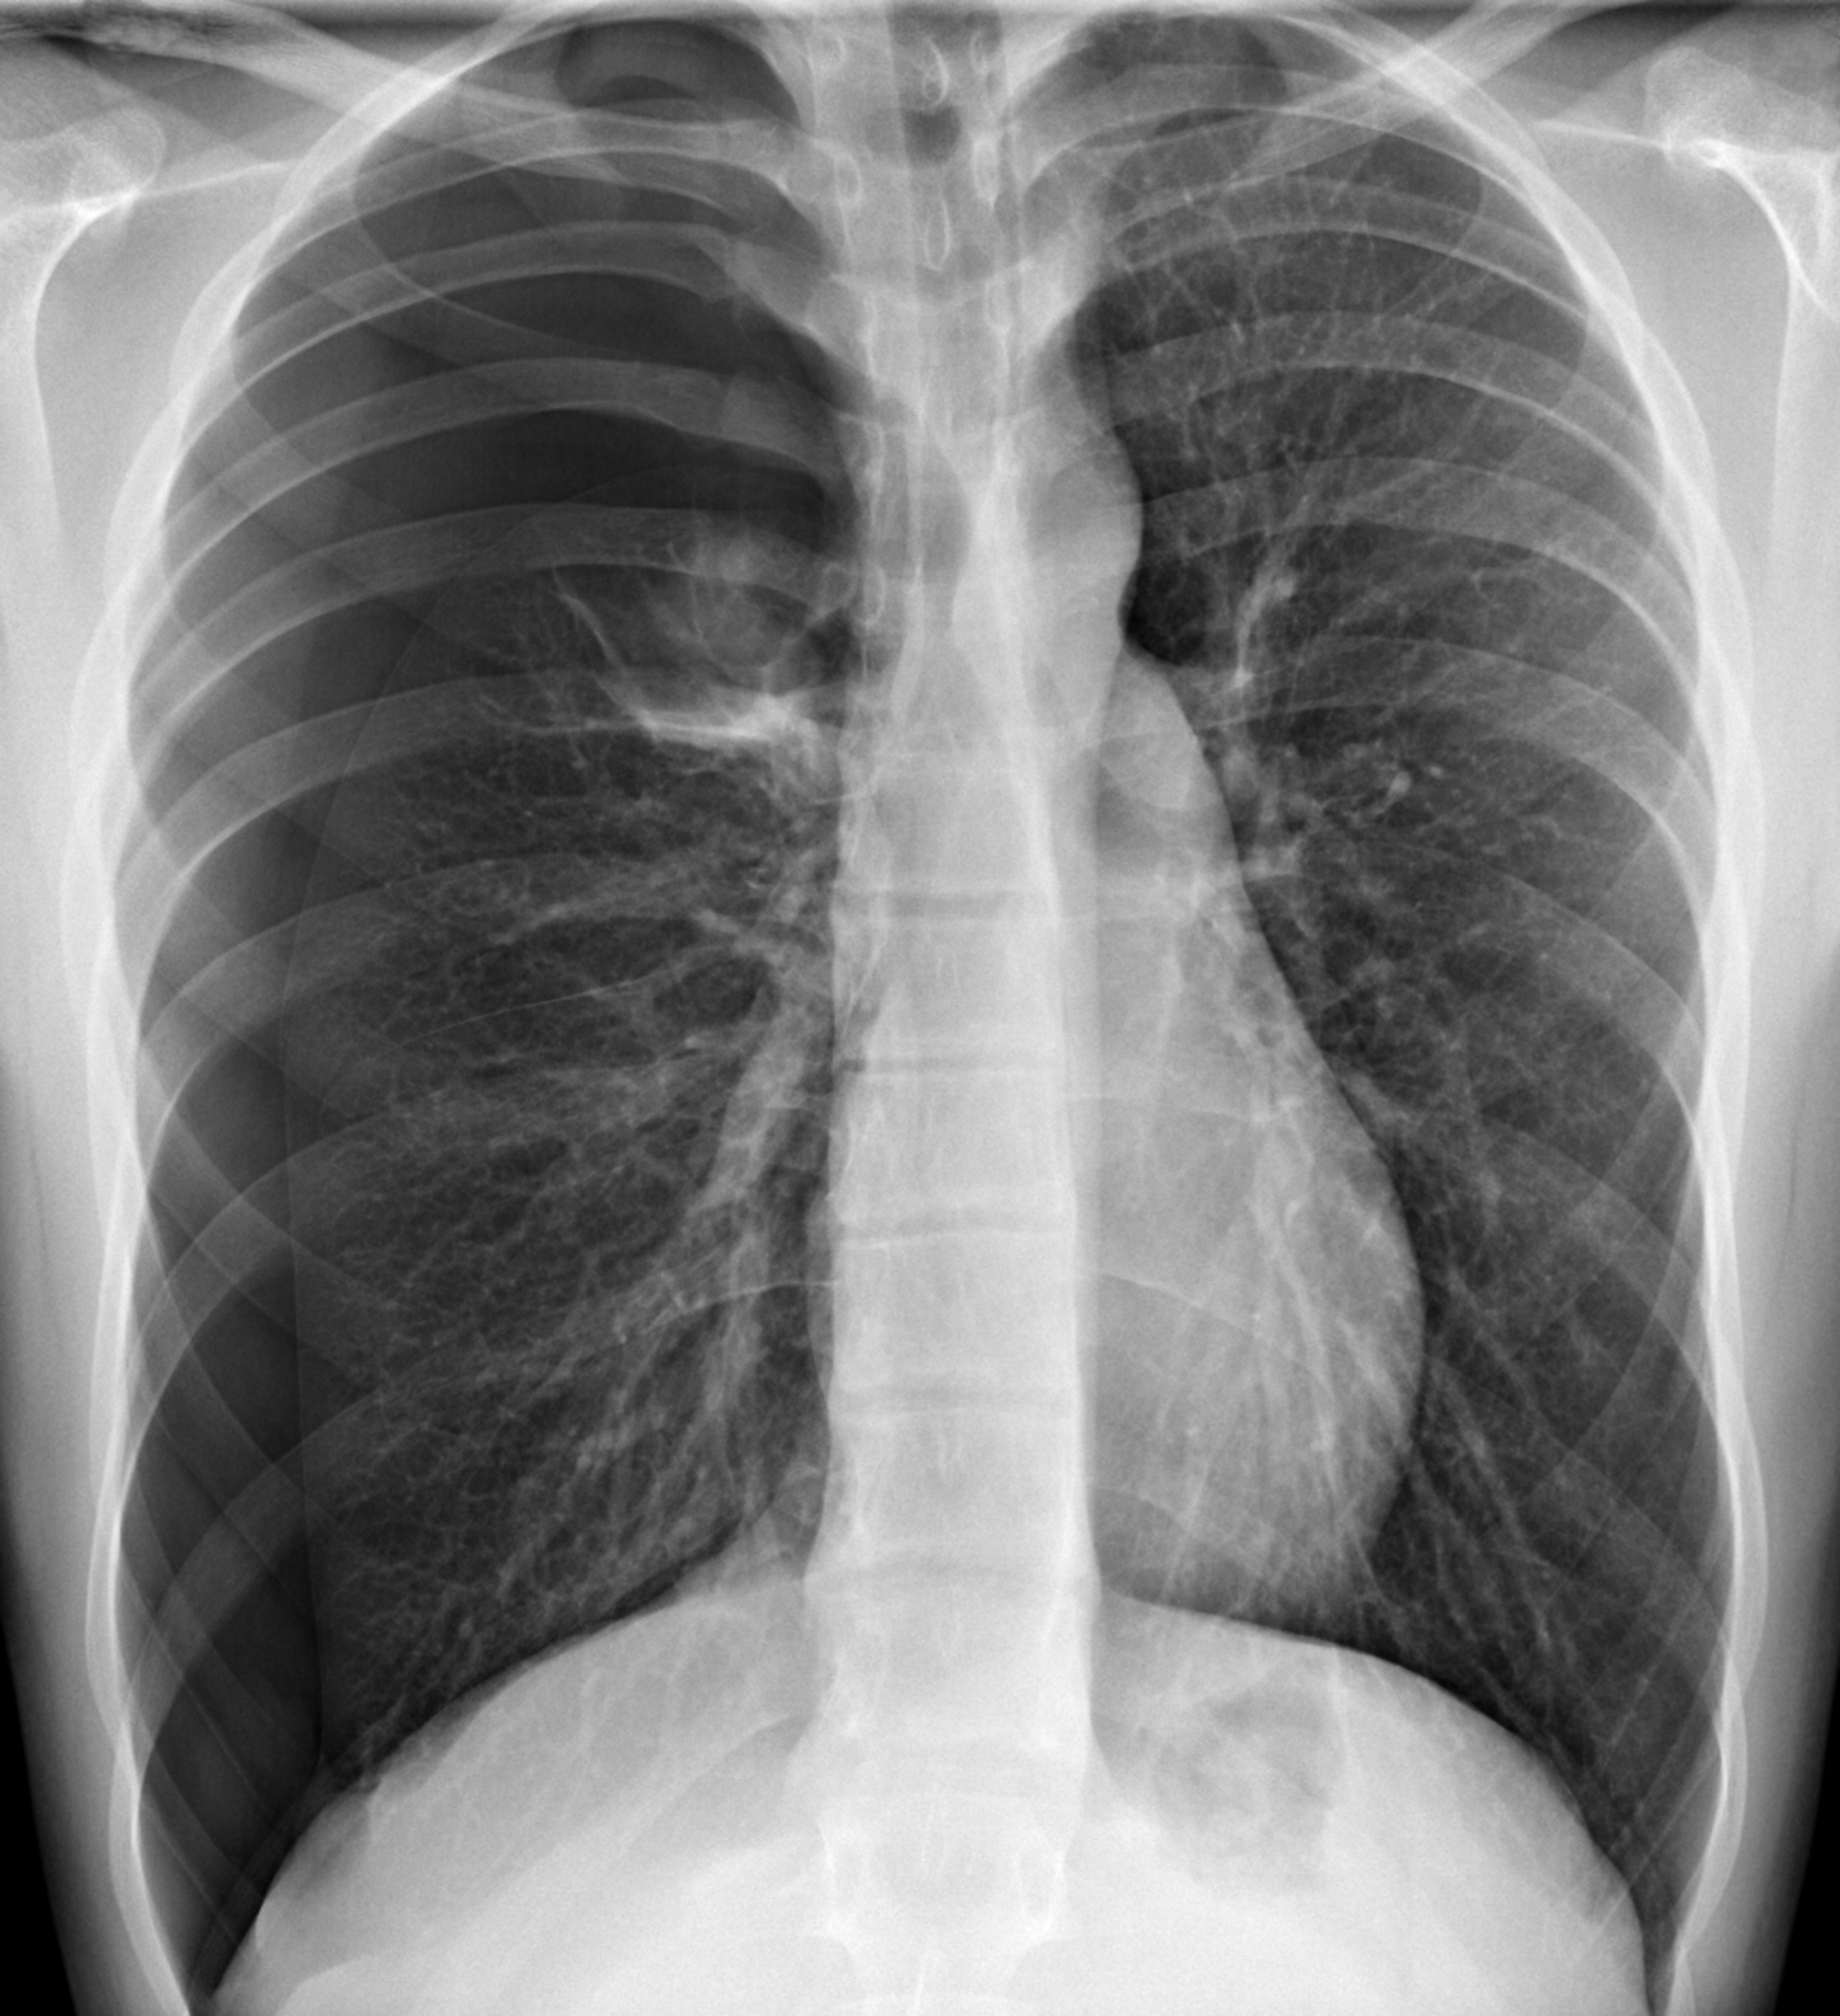

- Consiste en la interposición de una masa de gas (aire) entre la pleura visceral y la parietal. Generalmente cuando ocurre de forma súbita y en plena salud corresponde a la ruptura espontanea de una bula de enfisema la mayoría de las veces. En el tuberculoso produce un cuadro grave, pues se corresponde con el estallido de una caverna y da lugar a síndromes mixtos o hidroaéreos que invariablemente se complican por empiema de bacilo de Koch. Por último, pueden ser la traumática, la cual puede deberse a fractura costal, herida penetrante , biopsia pleural, etc.

En el neumotórax el espacio pleural está ocupado por aire que interfiere en la transmisión de los sonidos |

- Neumotórax a tensión se desarrolla cuando un lesión pulmonar o la pared torácica es tal que permita que el aire entre a la cavidad pleural, pero no salga fuera de ella (de una válvula de un solo sentido). Como resultado, el aire se acumula y comprime el pulmón, finalmente desplazar el mediastino, comprimiendo el pulmón contralateral, y el aumento de la presión intratorácica suficiente para disminuir el retorno venoso al corazón, provocando un shock.